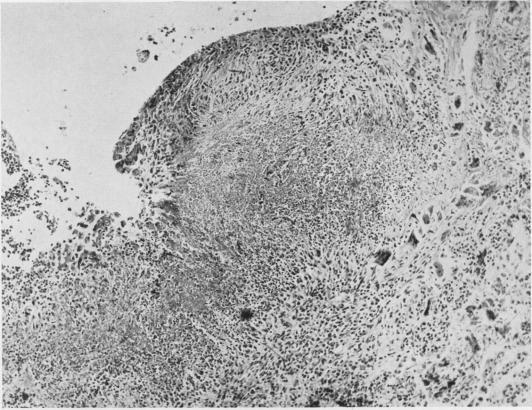

Rheumatoid lung changes associated with asbestosis.

Thorax. 1958 Sep;13(3):185-93. doi: 10.1136/thx.13.3.185.

Rheumatoid lung changes associated with asbestosis.类风湿性肺部改变与石棉沉着病相关。